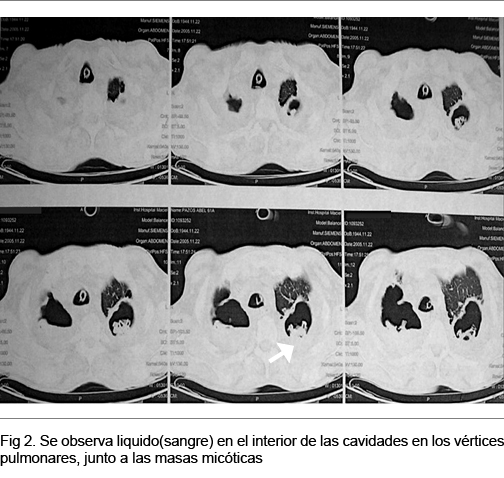

TAC tórax en CTI: en el primer día del episodio rojo (Figura 2): cavidades de LSD y LSI con sangre en su interior; cavidad paravertebral der. con líquido en su interior; masas intracavitarias biapicales.

TAC de Tórax (Control previo al alta de Sala de Medicina): masas micóticas intracavitarias (Figura 3) actualmente se controla en policlínica de Neumología, tratado con itraconazol 400 mg día v/o al alta, en espera para completar los estudios de valoración preoperatorio y optar por una alternativa quirúrgica.